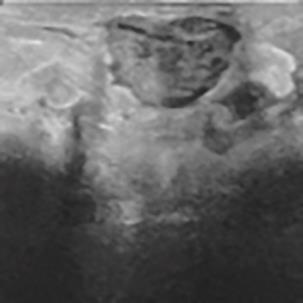

乳腺癌是全球女性最常见的恶性肿瘤之一,准确的病变分割对于乳腺癌的早期诊断与治疗具有重要意义。然而,由于病变形态的多样性以及超声成像机制的复杂性,现有基于深度学习的乳腺超声图像病变分割方法在分割准确性方面仍面临巨大挑战。为进一步提升乳腺超声图像中病变区域的分割精度,该文基于经典U-Net架构,提出了一种新型乳腺超声图像病变分割网络(CWSASKM-BBAM-Net)。首先,在网络中引入逐通道空间自适应选择核卷积模块(CWSASKM),根据不同通道的语义特征为每个空间位置自适应选择感受野大小,以增强多尺度信息的建模能力;然后,引入双向边界感知机制(BBAM),通过融合正向与反向注意力,对目标显著区域及其边界进行协同建模,同时逐步提升对非显著区域与病变区域的区分能力,以进一步强化边界信息的表达;最后,在3组公开乳腺超声图像数据集(BUSI、UDIAT和STU)上开展分割实验。结果表明:该方法在数据集BUSI上的杰卡德指数、精确率、召回率和Dice相似系数分别为71.97%、82.85%、81.40%和80.44%,较次优方法分别提升1.69、1.05、1.28和1.84个百分点;在数据集UDIAT上,这4项指标分别达到78.14%、88.31%、86.73%和86.10%,较次优方法分别提升了2.75、2.04、0.56和2.01个百分点;在外部数据集STU上,该方法也取得了优于其他方法的整体表现。实验结果表明,CWSASKM-BBAM-Net在乳腺超声图像分割任务中展现出更优的整体性能。